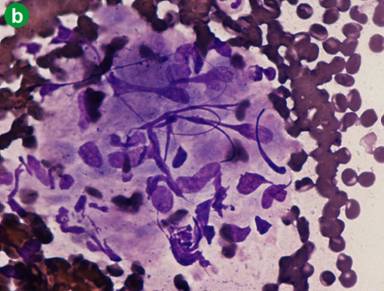

The patient also underwent a fine needle aspiration biopsy of the paratracheal subcarinal and hilar lymph nodes, which resulted negative for neoplastic cells, showing the presence of epithelioid granulomas suggestive of nodular sarcoidosis (Figure 3). A work-up for sarcoidosis was then carried out in order to make a differential diagnosis between pancreatic cancer associated with an atypical sarcoid-like reaction, or the presence of a pancreatic granuloma in the context of a systemic sarcoidosis. No ophthalmic or skin involvements at specific examinations were seen and angiotensin converting enzyme was within the reference range of our laboratory (10 µg/L; reference range: 6.1-21.1 µg/L).

Figure 3. Transbronchial needle aspiration was performed on mediastinal lymph nodes. The cytological picture consists of granulomas on a background of small, mature lymphocytes. Granulomas appear as small aggregates of epithelioid histiocytes, with relatively sharp borders. The background is clean with no appreciable necrosis. May-Grundwald Giemsa, (a. original magnification 600x); and the same appearance is observed in Diff Quik® (Diff-Quick Staining Protocol. Prepared by Roy Ellis: IMVS Division of Pathology, The Queen Elizabeth Hospital; Woodville, South Australia, Australia) stain for rapid-on-site-examination. A small, well defined granuloma is visible on a clear background (b. original magnification 600x). |